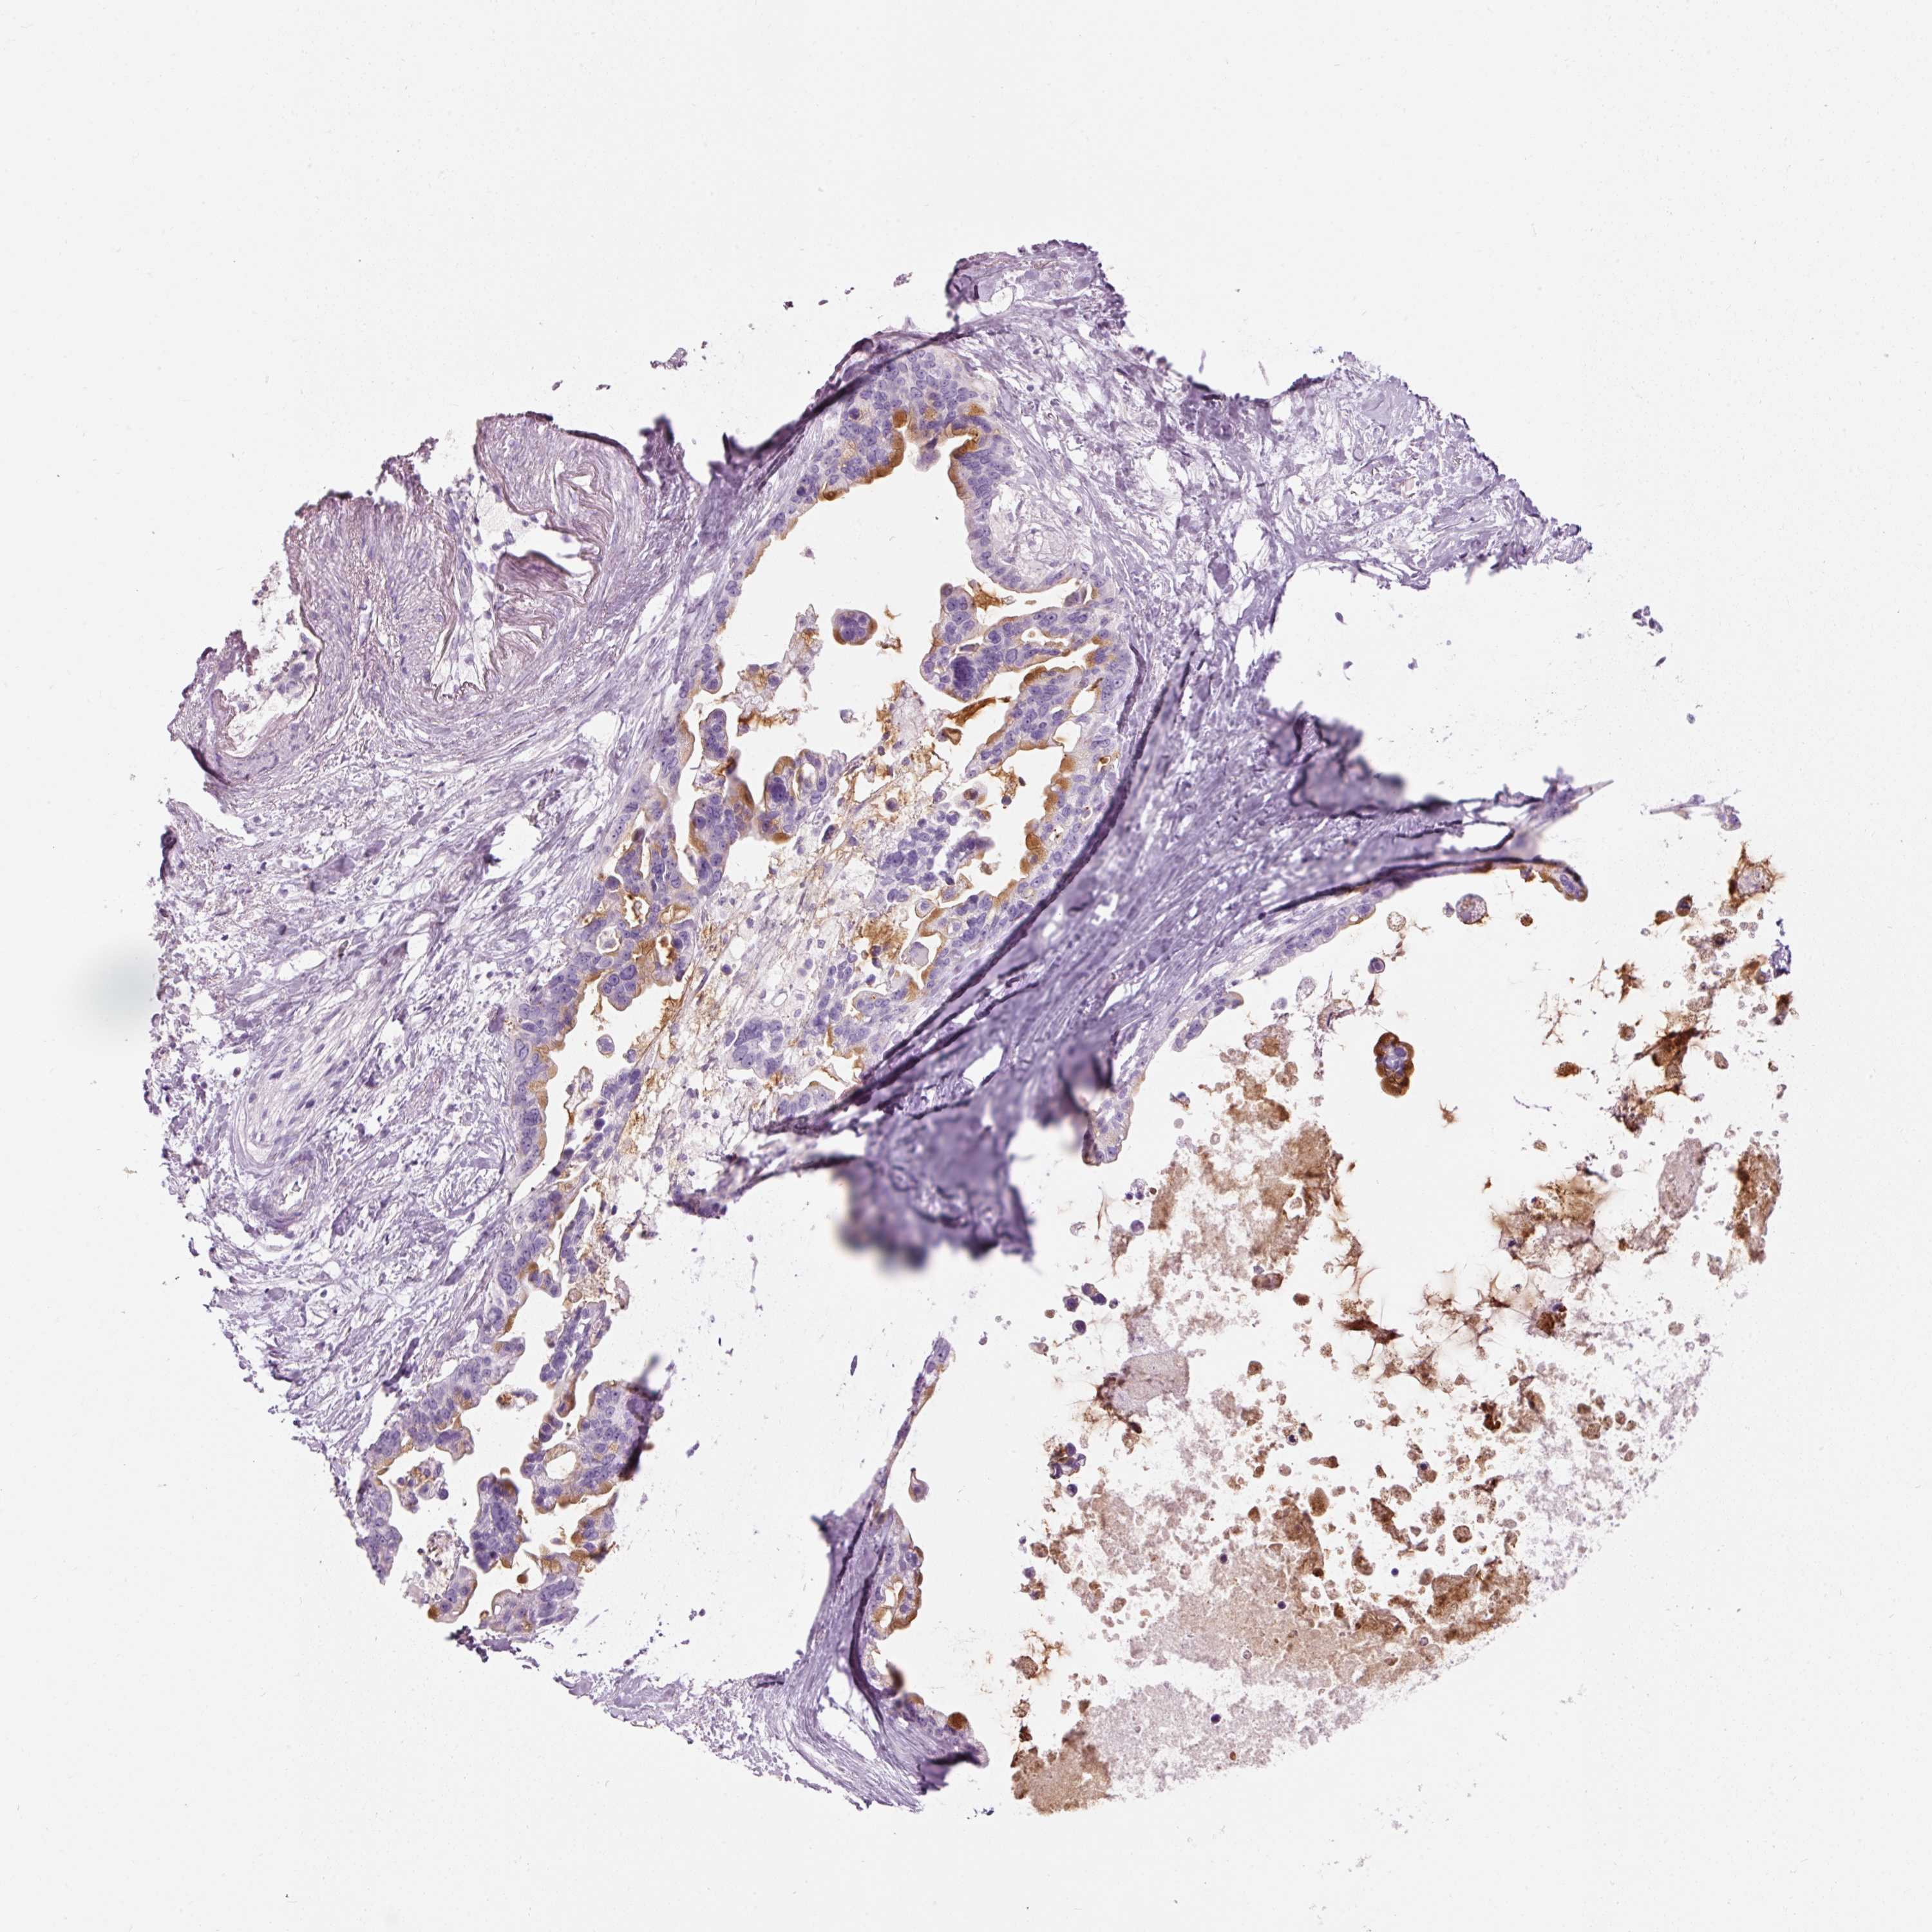

PANCREATIC CANCER - Protein expressioni

A mouse-over function shows sample information and annotation data. Click on an image to view it in a full screen mode. Samples can be filtered based on level of antibody staining by selecting one or several of the following categories: high, medium, low and not detected. The assay and annotation is described here.

Note that samples used for immunohistochemistry by the Human Protein Atlas do not correspond to samples in the TCGA dataset.

Antibody stainingi

Antibody staining in the annotated cell types in the current human tissue is reported as not detected, low, medium, or high, based on conventional immunohistochemistry profiling in selected tissues. This score is based on the combination of the staining intensity and fraction of stained cells.

Each image is clickable and will lead to virtual microscopy that enables deeper exploration of all samples and also displays staining intensity scores, fraction scores and subcellular localization as well as patient and tissue information for each sample.

Adenocarcinoma, NOS

Adenocarcinoma, metastatic, NOS